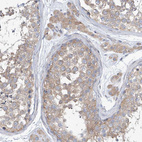

Immunohistochemical staining of human kidney, skeletal muscle, stomach and testis using Anti-UFL1 antibody HPA030560 (A) shows similar protein distribution across tissues to independent antibody HPA030559 (B).